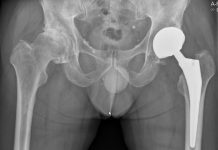

Ingreep heupprothese kan prima poliklinisch

Gezonde patiënten met artrose die in aanmerking komen voor een heupprothese, kunnen die ingreep heel goed in dagbehandeling ondergaan. Dat blijkt uit onderzoek van...